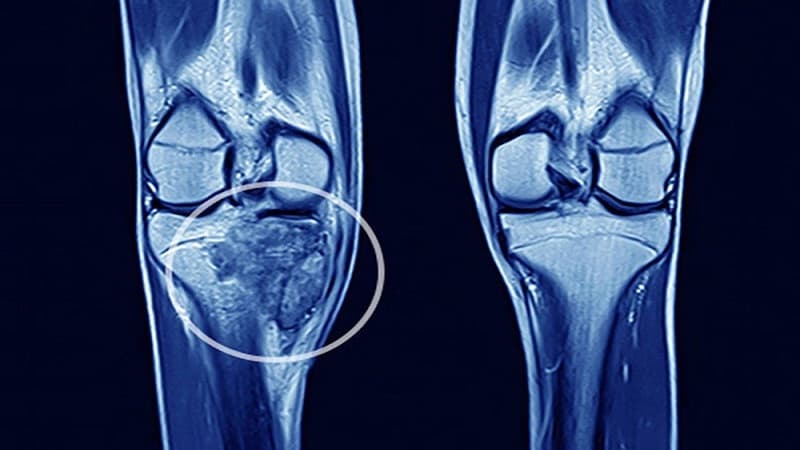

Trước mổ, bác sĩ xác định chính xác vị trí khối u sụn xương lành tính bằng các phương tiện chẩn đoán hình ảnh, đồng thời đánh giá mối liên quan với các cấu trúc lân cận như màng phổi để có phương án xử trí phù hợp.